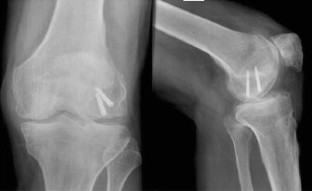

We report the case of an isolated, low energy, closed, displaced, lateral femoral condyle Hoffa fracture in a 54 year old Caucasian man. This was treated by open reduction and internal fixation using two headless compression screws. At 1 year review the patient was pain free, the fracture had radiographically united and there was a range of movement to his knee of 0°–100°.

Fig. 2